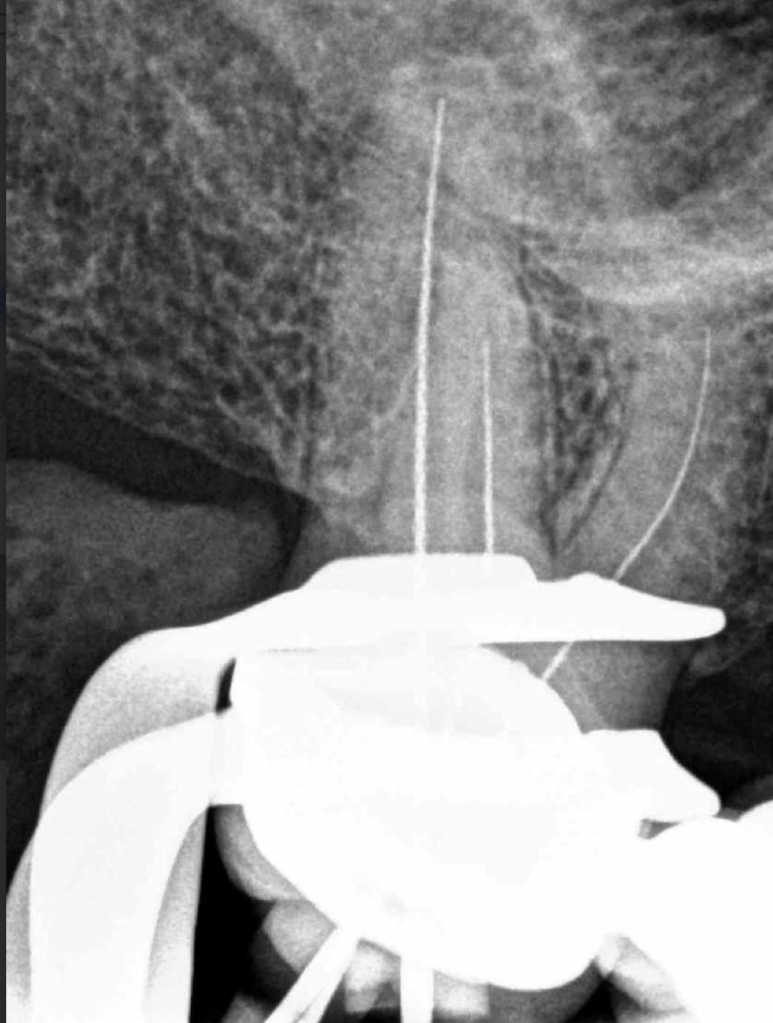

Pulpotomía biodentine + reco preendio